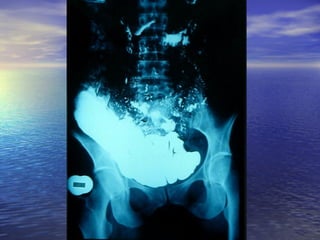

• Estudio radiológico consiste enEstudio radiológico consiste en

administración de 250ml oral de bario y laadministración de 250ml oral de bario y la

obtención de radiografías seriadas delobtención de radiografías seriadas del

intestino, realizadas a intervalos, hastaintestino, realizadas a intervalos, hasta

que el contraste llega al cielo.que el contraste llega al cielo.